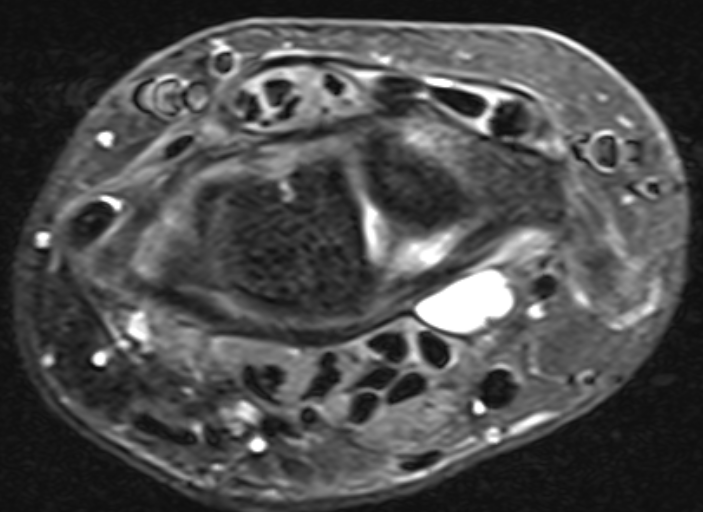

Volar ganglion